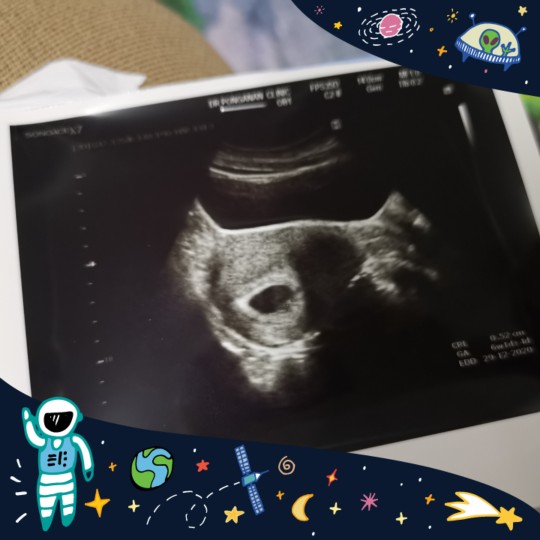

#ทีมธันวาค่ะ 29ธันวา